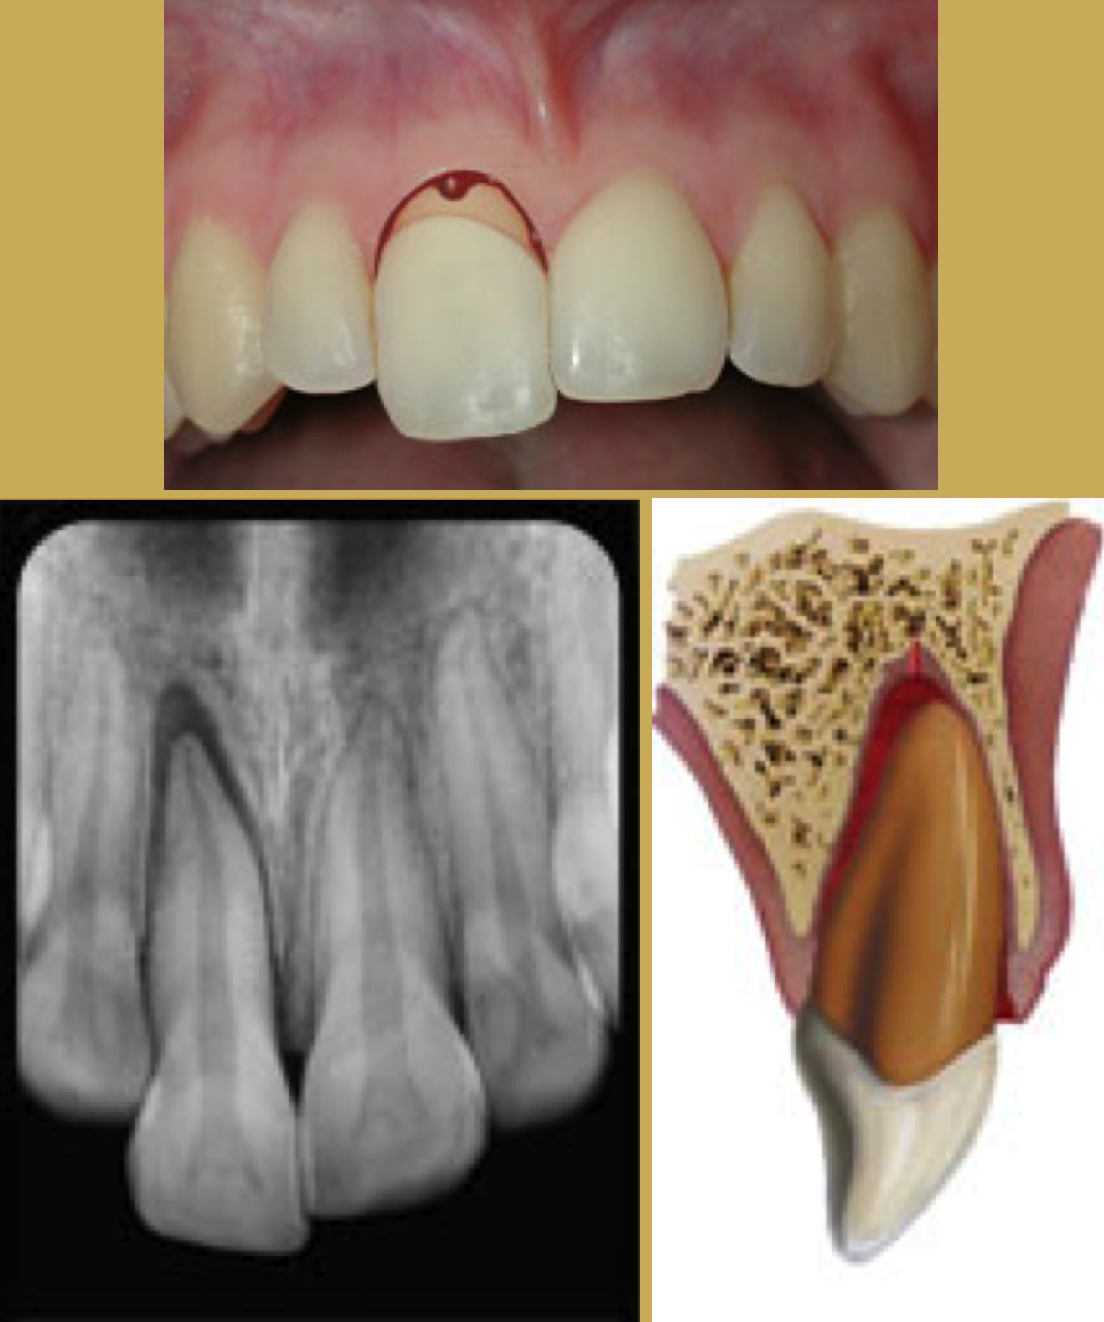

Tooth Extrusion

The tooth is displaced partially out of the socket by the trauma (Figure 4). It is usually displaced palatally. The athlete should then be asked to bite down on a sterile gauze pad to temporarily splint the tooth in preparation for transport. Immediate removal from participation and referral to a trauma-ready dentist or emergency facility.44

Radiographically the tooth appears dislocated and empty at the end of the socket. Treatment is to try to reposition gently - local anesthetic is usually not needed. Check the occlusion to be sure there is no pressure on the tooth and use a non-rigid splint for two weeks. The dentist should periodically monitor the vitality of the pulp and perform root canal therapy if needed.

Fig 4. Images of Extrusion

Figure 4